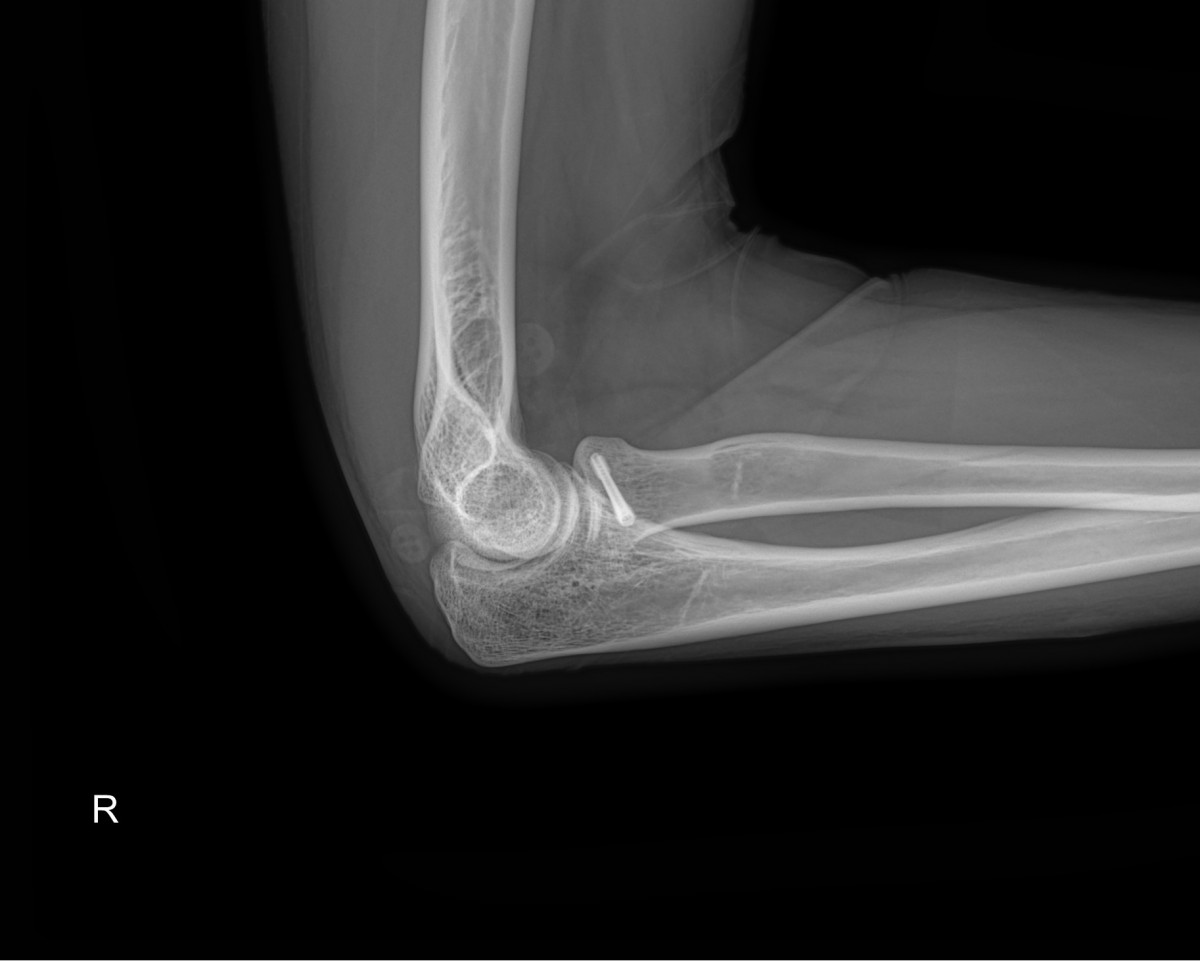

이재상원장님 팔꿈치 골절 수술 김시O 환자

dae765e4d9ac96aee867c9d6292d8784_1758001861_7767.jpg